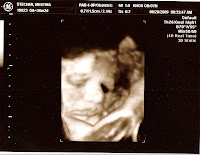

Here are pictures of the little sumo wrestler!

This morning was our last ultra sound for baby. After the ultrasound we had a non stress test and then a doctor appointment.

Everything looks good with the ultra sound. During the non-stress test the baby wouldn't move much so it took a little longer than usual, but things ended up looking good!

We asked how much the baby approximately weighs....

7 lbs. 12 oz. right now!!!!!!!!!!!!

She said that put the baby in the 90th percentile....we want average 50th percentile.